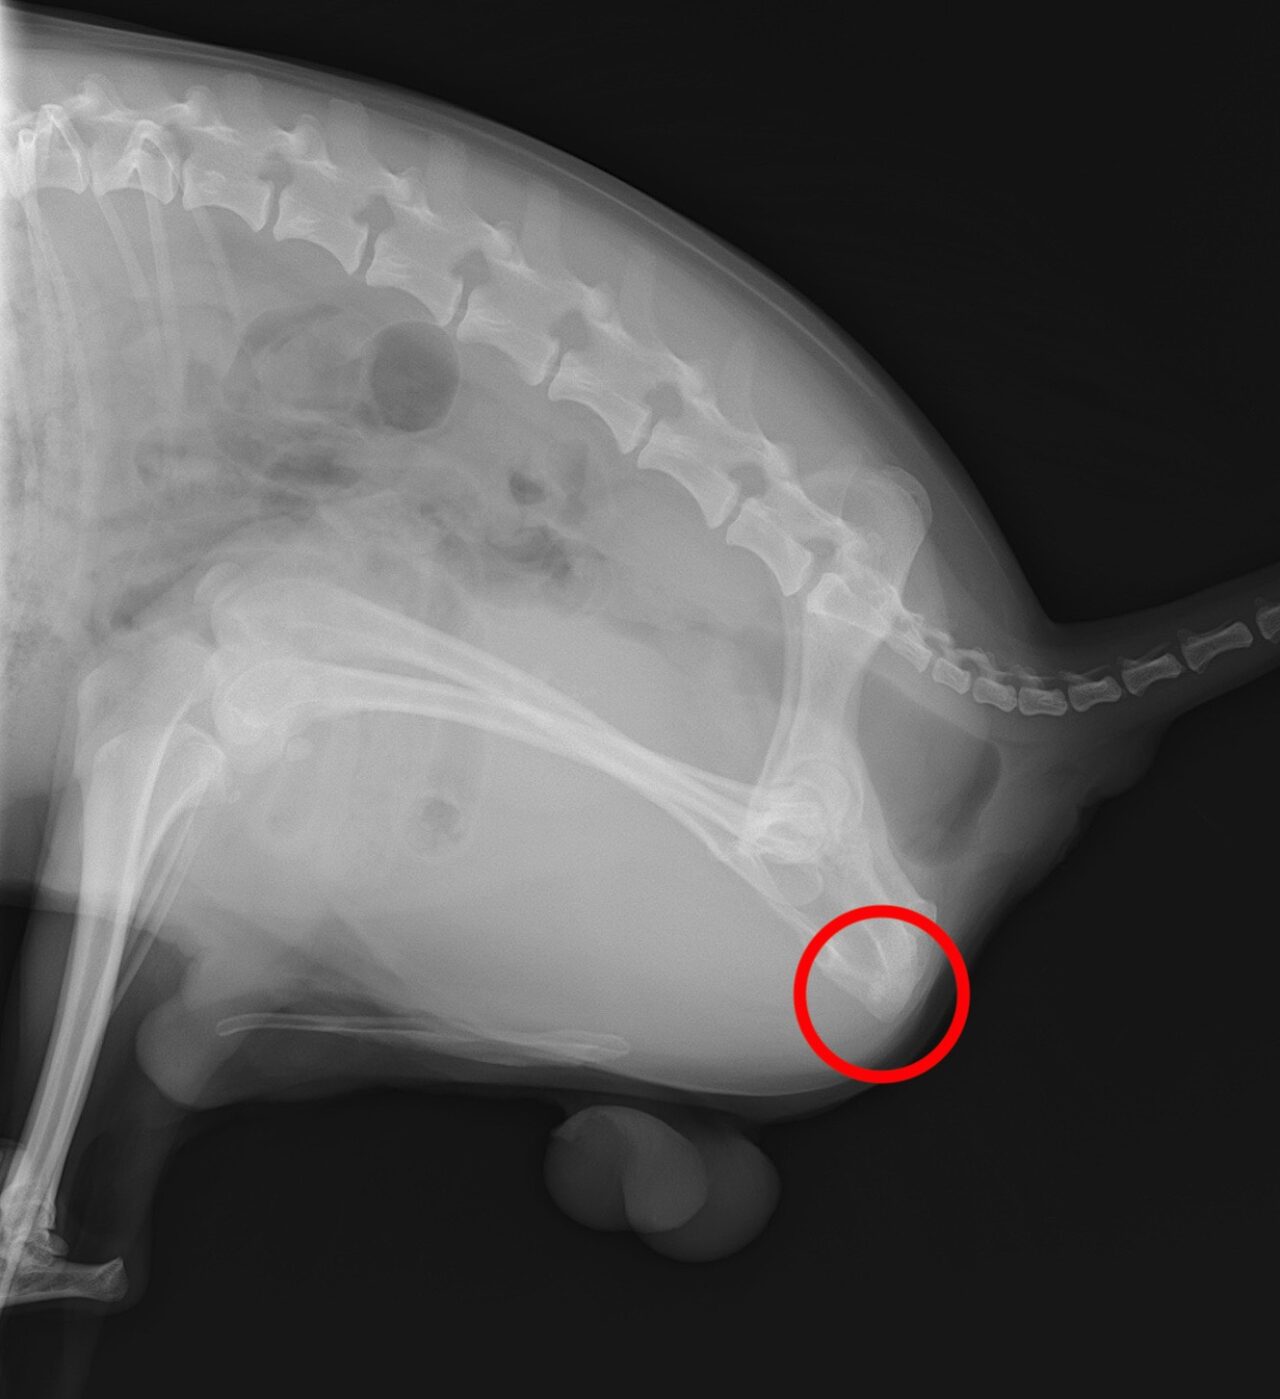

そこでレントゲン検査、腹部超音波検査を実施したところ膀胱内と尿道に結石を疑うような像が認められました。

レントゲン画像